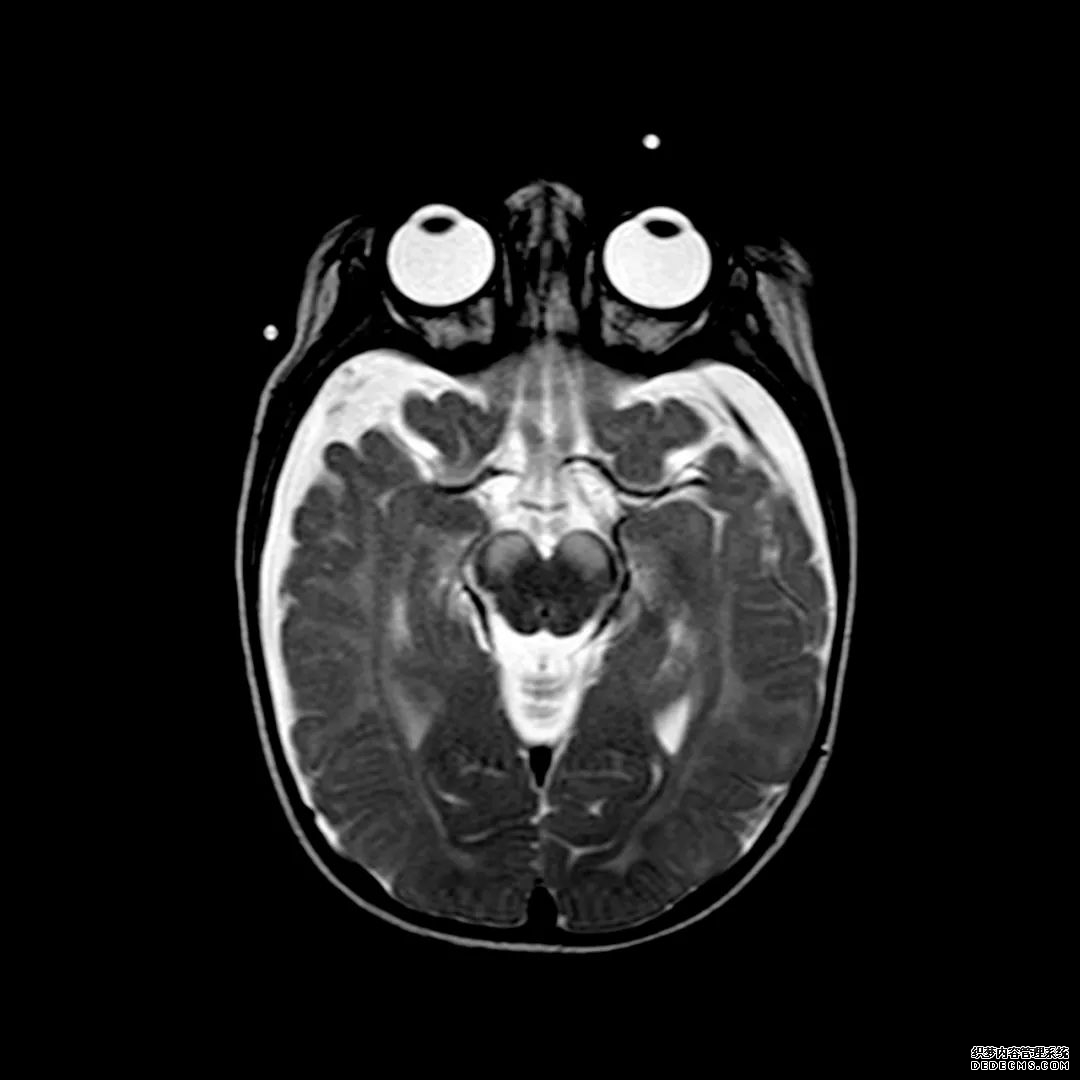

脑MRI显示尾状核、扁豆状核和脑梗头部T2/FLAIR呈双侧对称异常高信号。扩散限制涉及这些区域,其特征是扩散加权DWI(B-1000)上的高强度,ADC图上相应的减弱强度。

低血糖性脑病是一种代谢性脑病,它是由脑细胞对葡萄糖的供应和使用之间的不平衡引起的。脑MRI,尤其是DWI是诊断和预测该病预后的重要工具。

影像影响内囊后肢、大脑皮层(特别是枕叶和岛叶)、海马和基底节区,常是双边对称性的。